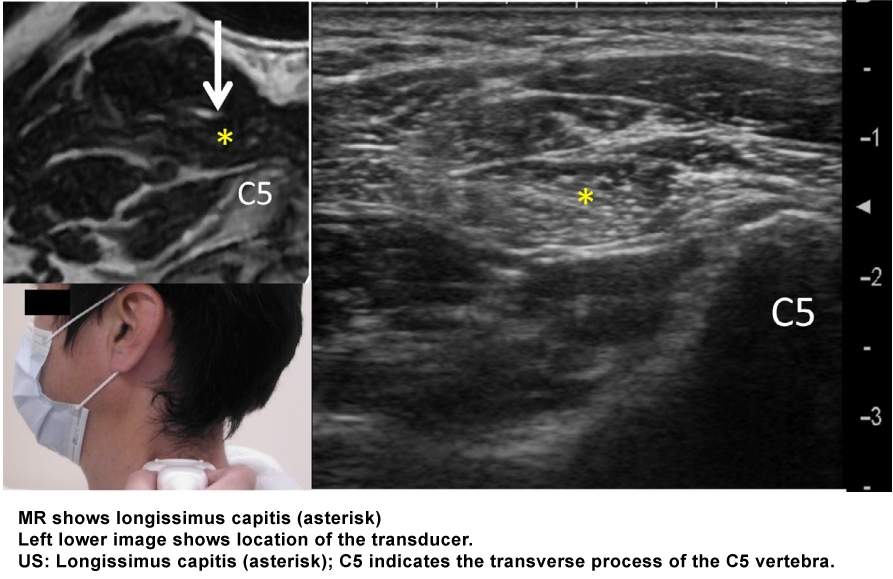

From: Mezaki T. Ultrasoundâ€guided botulinum toxin therapy for deep muscles in cervical dystonia. Neurol Clin Neurosci 2020; 8: 3–10.

Note that in the figure on the right, splenius capitis is transparent, allowing for the longissimus capitis to be seen deep to splenius.

The longissimus capitis lies between the longissimus cervicis (which is directly lateral to it) and the splenius capitis (which is directly medial to it).